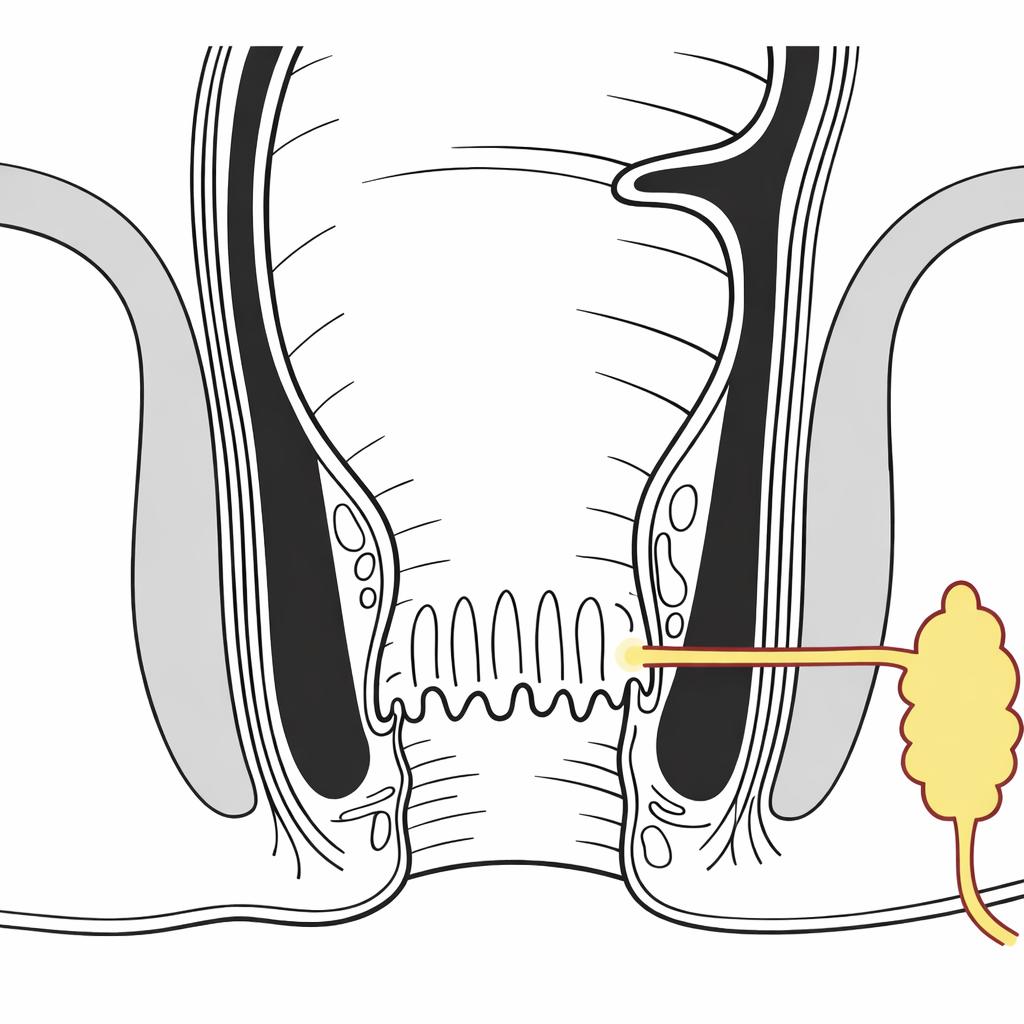

Piles

Advanced laser treatment for piles ensuring painless procedure and recovery.

- Advanced Laser Treatment

- Minimally Invasive Procedure

- Less Pain & Quick Recovery

- Short Hospital Stay

Anal Fissure

Effective fissure treatment relieving pain and bleeding during bowel movements.

- Laser Treatment for Chronic Fissure

- Safe & Effective Procedure

- Minimal Pain & Quick Healing

- Experienced Specialist Care

Anal Fistula

Modern laser fistula surgery ensuring safe treatment and faster recovery.

- Advanced Laser Fistula Surgery

- Minimally Invasive Technique

- Reduced Risk of Recurrence

- Faster Recovery Time